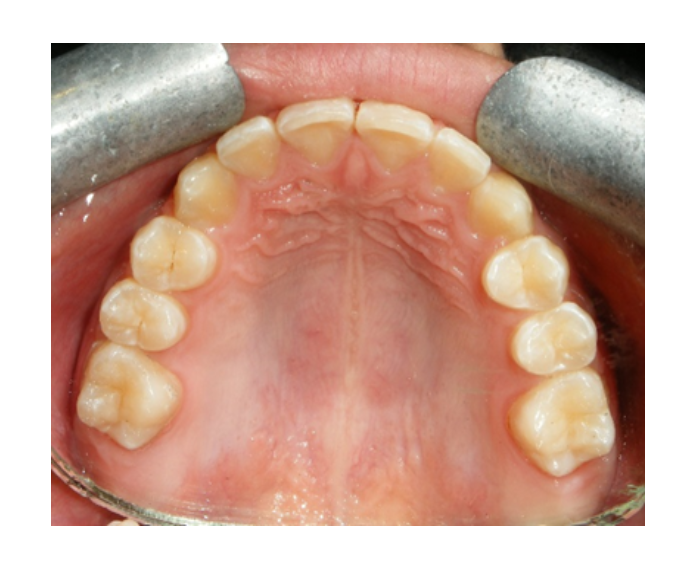

Prótesis fija de zirconia

sin metal